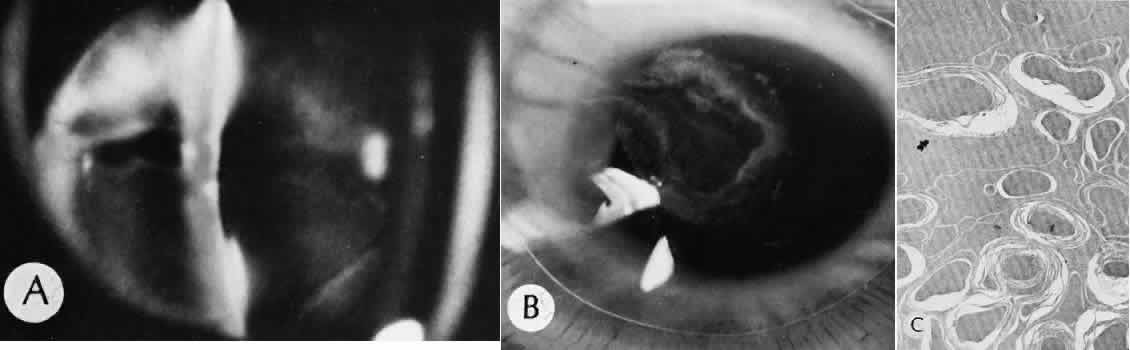

Cyclocryotherapy, cyclodiathermy (Fig. 20), and therapeutic ultrasonography apply energy directly to the pars plicata and cause lysis of the ciliary muscle and occlusion of the vascular supply, leading to extensive necrosis and scarring. Pressure lowering is accomplished by a reduction of aqueous production. Heat applied to the sclera may cause necrosis and localized scleral thinning. Cold applied to the sclera, unless extreme, does not cause any clinical or histologic changes.

Fig. 20. Cyclodiathermy treatment of the ciliary body to control glaucoma. A. Gross photograph illustrates extensive areas of depigmentation mainly in the region of the pars plana (arrows) rather than the pars plicata. B. Light micrograph of the region of the pars plana illustrates an extensive area of tissue degeneration of the pars plana (between arrows) in the late postoperative course. C. Light micrograph of the destructive effects of cyclocryotherapy also in the region of the pars plana and pars plicata. The ciliary epithelium in the early postoperative period is necrotic and cystic. (Hematoxin-eosin stain; A, × 8; B, × 16.)